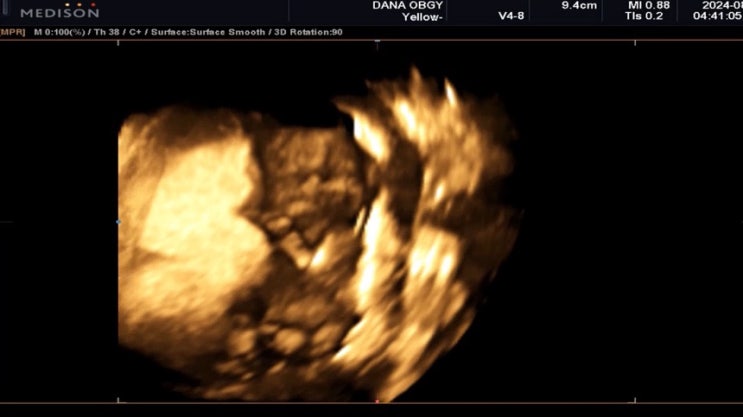

조보아 근황 공개 이후 반응 폭발…출산 후 첫 외출서 달라진 분위기 눈길

조보아 근황이 공개된 이후 온라인 반응이 빠르게 이어지고 있다. 배우 조보아는 최근 자신의 SNS를 통해 한…